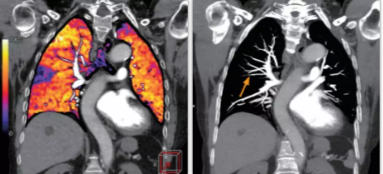

相比傳統(tǒng)成像方式,肺部柔性減影技術(shù)通過(guò)人工智能,對(duì)平掃數(shù)據(jù)和CT肺動(dòng)脈血管掃描數(shù)據(jù)進(jìn)行智能比對(duì),解碼并識(shí)別各個(gè)器官(肺、氣管、肺動(dòng)脈、肺靜脈、主動(dòng)脈等)的空間位置,并在三維空間中進(jìn)行體素級(jí)的柔性配準(zhǔn),從而極大提升了不同序列數(shù)據(jù)的空間位置的一致性。通過(guò)肺部柔性減影技術(shù)可得到肺強(qiáng)化碘圖,可以顯示出傳統(tǒng)CTPA圖像看不到的小栓塞病變,提高了栓塞檢出率,其結(jié)果甚至可與SPECT吻合。

肺智能柔性減影成像功能發(fā)現(xiàn)亞段肺栓塞

此次,佳能對(duì)能譜成像方案也進(jìn)行了升級(jí),結(jié)合了AI的柔性能譜技術(shù)從能譜技術(shù)的四個(gè)基本判別條件——輻射劑量,數(shù)據(jù)精度,覆蓋寬度和能量分離度著手,分別優(yōu)化了以上四種技術(shù),實(shí)現(xiàn)了kV和mA的獨(dú)立切換。高低kV的切換保證了能量分離度;根據(jù)體位自動(dòng)調(diào)整的mA有效降低了輻射劑量;16厘米容積探測(cè)器解決了覆蓋寬度的問(wèn)題;單球管配合AI感知掃描技術(shù)與AI器官柔性配準(zhǔn)算法,確保了數(shù)據(jù)精度。以此作為保障,佳能能譜+灌注的多模態(tài)成像方案僅需一次掃描即可同時(shí)獲得能譜數(shù)據(jù)和灌注數(shù)據(jù)。